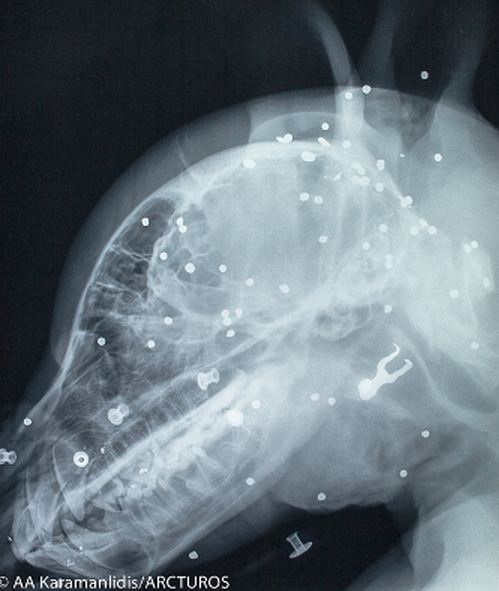

Μετά από κλινική εξέταση και τη λήψη ακτινογραφιών διαπιστώθηκε κρανιοεγκεφαλική κάκωση, ενώ παράλληλα βρέθηκαν και άφθονα βλήματα πυροβόλου όπλου στην περιοχή της κεφαλής και του θώρακα.